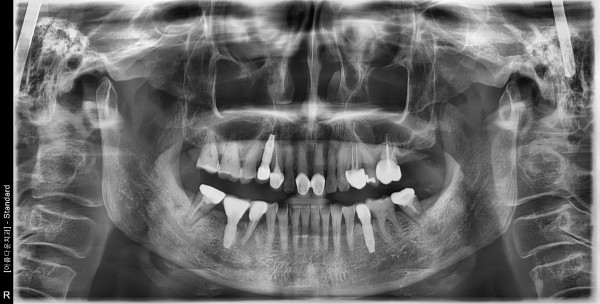

60대 여성 임플란트 식립